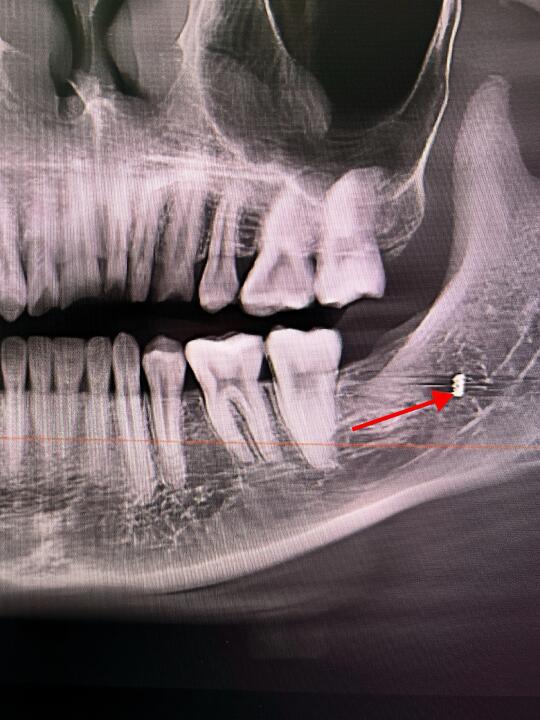

👨🏻⚕️今天有个美女过来找锤哥拔牙~ 👨🏻⚕️美女说有上次在诊所拔牙的牙片,锤哥看后说“还是在我们科重新拍一张牙片吧~” 🤣不拍不知道,一拍吓一跳,拍片后发现美女上次拔牙后,骨头里有个高密度影~ 👨🏻⚕️以锤哥多年的工作经验来看,这好像是折断在里面的「钻头」 🫣好在锤哥先复查了一个牙片,不然还真有点说不清了,话说那个诊所也是🐮B,骨头里留下这么长一根钻头,都不跟患者说,也不想办法取出来~ 👨🏻⚕️锤哥在这里奉劝大家,拔牙风险高,且拔且小心❤️啊!